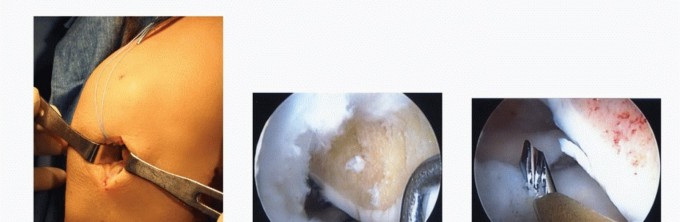

FIG 2

•

A.

AP weight-bearing bilateral knee views showing subtle medial compartment joint space narrowing of the right knee (

arrow

).

B.

MRI showing deficient medial meniscus.

C.

Arthroscopic image of right knee showing deficient medial meniscus.

A detailed history includes specific symptoms, prior injuries, and subsequent surgery. Arthroscopy pictures are helpful in determining the degree of meniscal resection and the condition of the articular cartilage.

Anteroposterior (AP) view of both knees in full extension (

FIG 2A

): Look for subtle joint space narrowing.

Magnetic resonance imaging (MRI): to assess menisci, articular cartilage, and subchondral bone (

FIG 2B

)

Diagnostic arthroscopy is often recommended.

It will accurately define the extent of meniscectomy and the degree of arthrosis if previous arthroscopic images are unavailable or unclear or if more than 6 months to 1 year has elapsed since the last arthroscopy (

FIG 2C

Outerbridge grade III or less articular cartilage damage is acceptable (grade I or II is preferable). A focal grade IV lesion may be addressed concurrently with a cartilage resurfacing procedure. Diagnostic arthroscopy may also assist in planning the optimal method for addressing the articular cartilage lesion.